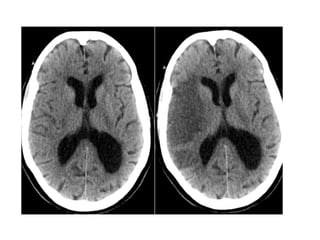

• Seizures

• Hydrocephalus